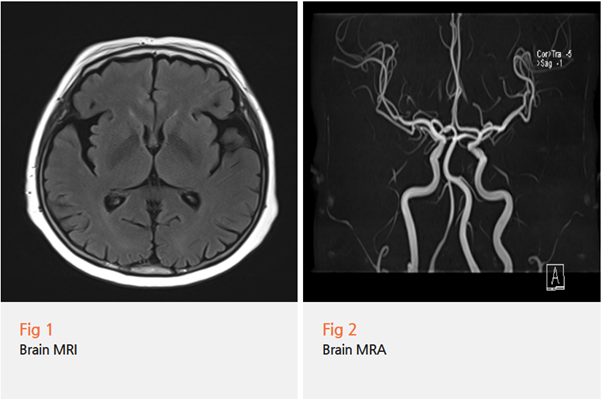

그림6.png 촬영 일시: 2024.10.11

<Fig 3. 척추 MRI>

검사 결과 요추협착증과

수술 부위 주변의 문제들이

통증의 주요 원인이었어요.

비수술적 치료를 통해

허리와 다리 증상도 상당히 호전시킬 수 있었고,

결과적으로 환자분의 전반적인

삶의 질이 크게 개선되었습니다.